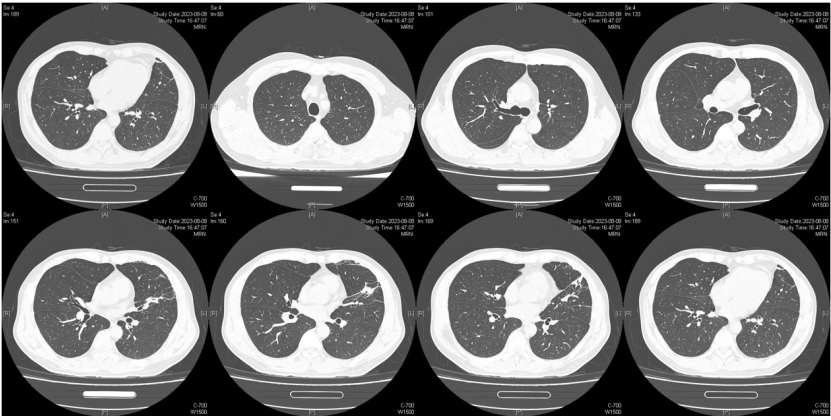

由于厌氧菌培养非常困难,既往我们对厌氧菌的认知仅限于在消化道定植,对其致病机制以及何种情况下致病并不非常清楚。厌氧菌定植于皮肤黏膜,是一种内源性微生物,感染发生率高,可导致严重、致死性感染。由于标本采集和转运的特殊性,使厌氧菌难以分离;加之其培养困难,体外生长慢,所以既往很难识别。厌氧菌在治疗方面存在一定挑战,如往往混合多重感染,且易产生耐药,也会因治疗延迟导致治疗失败。随着近10年来NGS技术的应用和普及,我们对厌氧菌的认识得以提升。常见的致病厌氧菌分为革兰阳性球菌、革兰阴性球菌、革兰阳性非芽孢杆菌、革兰阳性芽孢杆菌以及革兰阴性杆菌(表1)。革兰阳性非芽孢杆菌中可能致病的是放线菌,例如龋齿放线菌参与龋齿的发病过程。革兰阳性芽孢杆菌往往具有致病性,其中产气荚膜杆菌、艰难梭菌/难辨梭状芽孢杆菌、肉毒杆菌/肉毒梭菌、破伤风梭菌/杆菌具有强致病性。革兰阴性杆菌中的拟杆菌属对青霉素类药物具有很强的耐药性,易致青霉素治疗失败。临床中我们与厌氧菌的接触逐渐增多,对其特点也会愈发熟悉,对于临床诊断和治疗也会有所帮助。在NGS报告中通常会将检出的厌氧菌列为“C类”,定义为致病性C类—呼吸道正常微生态菌群,一般不导致感染。但当患者存在误吸风险时,需关注厌氧菌引起肺脓肿的可能。此时就需要针对患者的危险因素、临床表现、影像学、病原学以及气管镜下特点等进行综合分析。微小单胞菌最早是通过培养进行鉴定。瑞士2015—2022年132例病例报告的培养鉴定结果显示,血液中检出微小单胞菌37例(28%),肺内(肺脓肿、脓胸)检出29例(22%),总体病死率较低(5.3%)。国内周华教授团队开展的一项回顾性研究分析了2019年1月至2020年7月经病理活检和mNGS诊断的5例与微小单胞菌相关的慢性肺脓肿患者。患者的平均病程为6.5个月,共同特征是口腔卫生差,有酗酒史,且CT表现为边界不规则的高密度团块状实变影,并且在病灶中间可见液化性坏死,但没有发现气液平面或空腔,所以前期易被误诊为肺癌。下图1是该研究报告中病例3的肺部CT表现。时间点1:首次就诊时,左下叶可见团块状肺不张,伴周围磨玻璃样渗出病变,中心坏死不明显,可见细小空气囊泡影。时间点2:发病8个月时,可见大面积肺实变,增强CT示病灶内有液化坏死和小空洞。时间点3:经过3个月的有效抗厌氧菌治疗,病灶明显缩小,遗留空洞和纤维增殖病灶。图2是病例4的肺部CT表现。时间点1:患者首次就诊时,右上叶可见肿块样肺部实变影。时间点2:发病8个月时增强CT,可见实变明显增大,病灶内出现液化坏死。时间点3:经过3个月的有效治疗,病灶明显缩小,有残留空洞和纤维瘢痕样病变。由于通过影像学鉴别该病与肺癌具有挑战性,所以5例患者都接受了支气管镜检查和CT引导下经皮肺活检。5例患者经组织活检或支气管肺泡灌洗液(BALF)标本mNGS检测到微小单胞菌。病例: 女性, 67岁, 主诉"咳嗽咳痰2个月"。现病史:2个月前,患者家属感染新冠病毒(家属新冠抗原阳性)之后,患者出现咳嗽咳黄脓痰,无痰中带血及痰液拉丝,痰无臭味,无胸闷气短及胸痛,无咽痛咽痒,无鼻塞流涕。6月9日于当地市医院住院,住院期间出现发热,体温最高38.6℃,无寒战,查新冠病毒核酸阳性,予先诺特韦/利托那韦片口服治疗。查胸部CT见左肺上叶软组织影,左肺上叶炎症。诊断肺脓肿,予头孢唑肟联合莫西沙星,治疗后复查胸部CT(6月26日)病灶较6月9日明显吸收好转。6月14日气管镜检査见左肺上叶支气管开口狭窄,见大量脓性痰液堵塞支气管开口(病原学结果家属无法提供)。6月30日办理出院后仍有咳黄脓痰,无发热畏寒,口服止咳化痰药物,未使用抗生素。7月30日复诊胸部CT见左肺上叶异常密度较前增大。8月2日再次于当地市人民医院住院。8月4日气管镜检查: 左肺上叶黏膜肿胀肥厚, 管腔狭窄, 见大量白色干酪样分泌物涌出, 支气管镜不能进入。内科予莫西沙星静滴治疗10天, 外科予莫西沙星联合哌拉西林他唑巴坦静滴9天。复查胸部CT见病灶较前进展, 且右肺出现新发感染病灶。病程中患者饮食可, 睡眠差, 二便正常, 体重减轻5 kg。既往对阿莫西林过敏, 表现为口服阿莫西林后全身皮疹。否认嗜酒史及吸烟史。入院后胸部增强CT可见病灶内液化坏死,同时伴有小的空气囊泡影(图3)。患者有胸痛症状。气管镜检查发现气道内有痰栓或黏液栓阻塞征象(图4)。灌洗液tNGS结果回示:微小单胞菌(序列数2762),巨细胞病毒(序列数171),副流感病毒(序列数79),EB病毒(序列数61)。考虑病毒不会导致气道内如此改变,但由于微小单胞菌属于常见口腔定植菌,此时也不能完全确定微小单胞菌是否为引起感染的主要责任病原体。8月24日起予莫西沙星0.4 g qd ivgtt+哌拉西林他唑巴坦4.5 g q8h ivgtt。经过上述治疗,患者局部病灶有所吸收,但整个肺叶并无明显改善(图5)。气管镜检查仍然发现气道内有较黏稠的黏液栓阻塞气道开口(图6)。治疗经过:气管镜下予以局部冲洗,再次送检tNGS。9月7日结果回示:微小单胞菌(序列数6464),较前明显增多;副流感病毒(序列数998),EB病毒(序列数331)。9月9日起调整治疗方案为美罗培南1 g q8h。9月12日复查患者胸部CT,可见肺通气部分改善,肺组织内实变较前吸收(图7)。第三次气管镜检查仍可见少量痰栓嵌塞在远端支气管开口(图8)。患者此后转入医联体医院继续抗感染治疗。病例2:女性,54岁。主诉:咳嗽咳痰2个月,发热1周。现病史:入院2个月前,患者在西南地区旅游时感冒,出现咳嗽咳痰,白痰为主,量多,无胸痛,无发热,无痰中带血,咳时气短。于河北某诊所间断输液治疗14天(具体不详),期间口服中药治疗,症状未缓解。入院3周前(2023-09-07)就诊于当地县医院,查胸部CT提示右肺炎症,静脉滴注氨曲南、左氧氟沙星、氨溴索治疗1周,症状未缓解。2023年9月14日复查胸部CT显示右肺炎症较前加重,于当地中心医院住院。动脉血气分析:pH 7.43,PaCO2 38.4 mmHg,PaO2 67 mmHg,SaO2 94.2%;血沉90 mm/h;生化:白蛋白35.3 g/L;CRP 82.7 mg/L;血常规:WBC 9.75×109/L,NEU 6.83×109/L,HGB 104 g/L。静脉滴注莫西沙星。入院10天前,行肺穿刺活检,病理回报为少量肺组织及纤维结缔组织,炭末沉积,较多中性白粒细胞、淋巴细胞及浆细胞浸润,伴脓肿形成;肺穿刺mNGS结果回报:微小单孢菌(序列数2650),鲍曼不动杆菌(序列数17),人类疱疹病毒4型(序列数60),人类疱疹病毒7型(序列数5),文氏密螺旋体(序列数4337),解卵磷脂密螺旋体(序列数1121),齿垢密螺旋体(序列数698)。调整抗生素为头孢哌酮舒巴坦2 g q12h。入院1周前,出现发热,体温最高38.5℃,不伴寒战,咳嗽咳痰无加重,无咯血;复查血常规、PCT、CRP均明显增高(未见报告单);复查胸部X线提示右肺炎症范围增大,右侧胸腔积液。更换抗生素为哌拉西林他唑巴坦4.5 g q8h。4天前,支气管镜下见右肺下叶背段支气管略狭窄,黏膜水肿,可见脓性分泌物溢出。BALF革兰染色查见革兰阴性杆菌,抗酸染色、霉菌未见异常,培养未回报。患者体温逐渐降至正常,咳嗽咳痰有所减轻,复查胸部CT提示右肺高密度影,右侧胸腔积液较前增多。为求进一步诊治来我院就诊被收入院。既往甲状腺功能减退病史5年,目前口服优甲乐治疗,监测甲状腺功能指标在正常范围。20年前因宫外孕行手术治疗。2023年10月8日胸部CT示胸膜下斑片状坏死,纵隔窗可见微小空气囊泡影及密度不均匀液化坏死(图9)。治疗:9月28日至10月13日莫西沙星0.4 g qd ivgtt+哌拉西林他唑巴坦钠4.5 g q8h ivgtt。最终患者病灶吸收好转并顺利出院。患者男性,42岁。主因间断咳嗽、咳痰1月余,左侧胸痛、气短2天入院。现病史:入院前1月余(2022-07-19),患者无明显诱因出现咳嗽,咳白痰,痰中有少量鲜红色血丝,左侧胸痛(为钝痛),深吸气后加重,就诊于当地医院。完善肺动脉CTPA:示左上肺动脉舌段分支局部管腔可见线条样低密度充盈缺损,考虑肺栓塞;左肺上叶实性病变伴不均匀强化,性质待定,部分为肺梗死改变可能,纵隔多发稍大淋巴结,性质待定;右肺下叶后基底段可见一不规则实性结节,边缘可见多发毛刺,直径约0.7 cm。当地医院考虑肺栓塞不除外,肺部感染?右肺下叶结节,予莫西沙星抗感染,低分子肝素抗凝,乙酰半胱氨酸化痰。完善CT引导下肺穿刺活检,病理示:肺泡腔扩张伴上皮轻度增生,肺泡间隔纤维组织增生伴散在炎细胞浸润,未见恶性病变。院外规律应用甲磺酸艾多沙班60 mg bid抗凝,先后间断应用左氧氟沙星0.5 g qd、头孢类抗生素(具体药物、剂量不详)抗感染。患者仍有间渐咳黄白痰,量不多,痰中有少量鲜红色血丝;无畏寒、发热、胸痛、夜间阵发性呼吸困难症状,无尿少、双下肢水肿,无口干、咽干,无牙齿成片脱落,无晨僵、关节肿痛,周身无皮疹,无盗汗乏力。2天前(2022-09-16)患者无明显诱因再次出现左侧胸痛,疼痛剧烈,深吸气、咳嗽及改变体位时加重,伴气短,就诊于我院急诊。完善肺动脉CTPA:肺动脉主干及其各叶段分支未见明显充盈缺损,左肺上叶舌段团块影,最大截面约7.6 cm×5.3 cm,边界不清,周围可见晕征;增强扫描不均匀强化,邻近胸膜增厚,性质待定,建议穿刺活检;纵隔及左肺门多发淋巴结显影。血细胞分析:WBC 11.09×109/L,NEU% 80.8%,NEU 8.95×109/L;CRP 54 mg/L,PCT 0.07 ng/ml。患者自发病以来,精神状、食欲及睡眠均一般,大小便正常,体重下降5 kg。2022年9月14日外院胸部增强CT:胸膜下楔形的影像学表现可见少量小气泡囊以及液化坏死病灶(图10)。初始考虑肺部肿瘤及肺栓塞。经过初步抗感染及抗凝治疗,患者病情无缓解,2022年9月27日患者突发胸痛,下肺影像加重并且出现脓胸(图11)。行胸腔穿刺并将脓液送检mNGS,结果回报:牙龈卟啉单胞菌(序列数3)。尽管序列数很低,但考虑是脓肿穿刺结果,因此考虑该菌致病可能。抗厌氧菌治疗:9月16-28日莫西沙星0.4 g qd ivgtt,9月23日-10月12日美罗培南1 g q12h ivgtt,9月28日-10月8日万古霉素1 g q12h ivgtt,10月13-18日莫西沙星0.4 g qd ivgtt+甲硝唑0.5 g tid ivgtt。患者肺脓肿的整体治疗时间约为3个月,病灶逐渐吸收,最终形成一些纤维索条影(图12,图13)。1年后复查病灶基本吸收(图14)。图14 1年后复查胸部CT(2023-08-08)微小单胞菌和卟啉单胞菌这两种厌氧菌在临床中需要引起重视,它们容易引起肺脓肿/脓胸。2024年国内学者Li Yao等在Diagn Microbiol Infect Dis 杂志发表了一篇牙髓卟啉单胞菌感染所致肺脓肿的病例报告,文章也提到在胸水或肺组织活检中,通过mNGS同时检出了微小单胞菌和卟啉单胞菌感染引起的肺脓肿。文章还回顾总结了既往发表的厌氧菌感染引起肺脓肿的病例,2010年报道的是1例脑脓肿患者,2019年报道1例脑炎患者,2022年报道1例脓胸伴呼吸衰竭患者。3例患者预后都比较好,可见厌氧菌亦可导致肺外多部位感染。对于厌氧菌所致肺脓肿的诊断及其引起的脓胸,目前的文献报道仍然较少,我们对它们的认知也有限,因此也提醒大家关注相关疾病的诊断和治疗。我们也已将本研究小组8例微小单胞菌所致肺脓肿的系列病例的研究结果发表(Front Cell Infect Microbiol, 2024, 14: 1416884),可供需要的同行参考。对于厌氧菌感染,我们需要提高警惕。厌氧菌往往在口咽部定植,其引起的脓肿/感染往往多为亚急性或慢性起病。患者通常有发热、胸痛症状,脓肿会逐渐进展。由于厌氧菌与人体本身是一种长期共生的关系,人体对厌氧菌的免疫识别可能处于较低的防御反应状态,所以会形成一个亚急性或慢性的发病过程。通常情况下,因厌氧菌的菌群发生了移位,从卫生条件不好的口腔扩展到相对无菌的肺内,同时开始增殖,由此可能导致感染。因此,对于酗酒以及口腔卫生非常差的人群,我们要重视对其风险因素和病史的排查。患者就诊时可能病情并不重,有胸痛或咯血,很容易误诊为肺部肿瘤,往往在这种情况下进行肺穿刺或气管镜检查,mNGS可以发现较大序列数的厌氧菌。但在mNGS检出厌氧菌后的诊断过程中又容易形成误判——究竟是致病菌,还是定植菌?此时结合患者其他病史和影像学特点(有脓肿/痰栓形成,微小空气气囊泡影),可能提示厌氧菌感染。然而,厌氧菌感染在病原学和影像学诊断方面仍然存在诸多困难,极易漏诊和误诊。微小单胞菌感染患者在气管镜下可以看到典型的脓性分泌物嵌塞气道,导致气道阻塞,也会造成远端气道和肺泡引流障碍。所以,及时处理气道内痰栓,改善引流,可能是使患者获得良好预后的关键。厌氧菌肺脓肿的吸收比较缓慢,抗感染的疗程也比较长,需要在后期诊疗过程中密切随访和观察患者对治疗的反应以及耐药等问题,及时调整治疗方案,适当延长疗程。